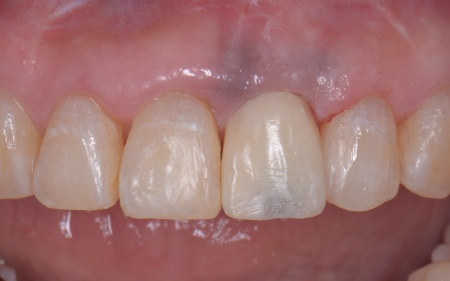

拝見したところ、左上前歯(中切歯)は被せ物で治療が施されていたものの、歯と歯茎の境目がほかの歯よりも上方にあり、歯が長く見えています。

また、インプラントに装着する被せ物は、強度と審美性に優れた白い素材のジルコニアセラミッククラウンを選択しています。

後日、完成したジルコニアセラミッククラウンを装着し、噛み合わせや見た目に問題がないことを確認して、治療を終了しました。